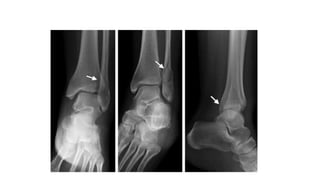

Đọc XQuang

AP

•Tibiofibular clear space : >5mm là bất

thường--> gợi ý tổn thương syndesmosis

•Tibiofibular overlap : <10mm là bất thường-

-> gợi ý tổn thương syndesmosis

•Talar tilt : > 2mm được xem như bất thường

Lateral view

• Gãy mắt cá sau

• Xương sên bán trật ra trước hoặc sau so với xương chày

• Di lệch và chồng ngắn của xương mác

• Các tổn thương phối hợp nếu có

Mortise view